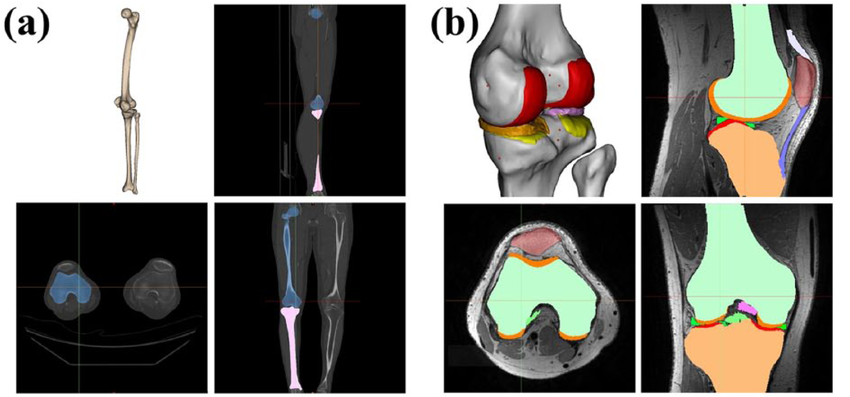

该项目旨在开发一种融合CT和MR多模态影像的膝关节骨与软骨的三维模型重建技术。拟通过理论和实验方法,将目前固定规格为主的膝关节假体设计,通过计算机辅助处理使之变得个性化和人性化,从而更加符合膝关节术前规划的假体设计需求,提高手术的精准性和患者的术后满意度。

膝关节骨与软骨重建